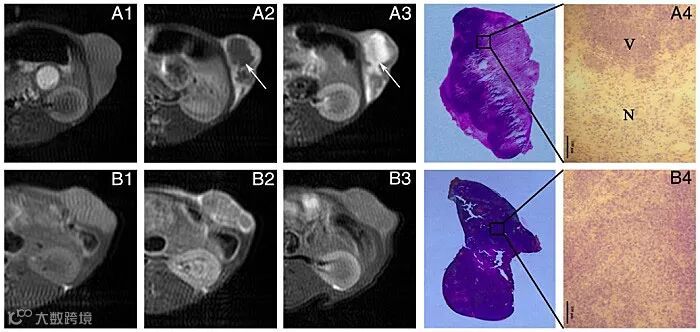

最后研究团队亦成功实现了GdL1对血管阻断药物CA4P治疗荷瘤大鼠W256皮下移植瘤的效果评价。肿瘤大鼠给予GdL1后3 h成像,肿瘤坏死中心显著增强,表明GdL1能够积累在CA4P治疗后的肿瘤坏死中心,具有早期评估CA4P治疗效果的潜力。肿瘤坏死是多种肿瘤治疗手段的治疗结果,包括血管阻断剂、化疗栓塞、射频消融及微波消融等。介于GdL1优异的成像性能及合成方法,有望将其应用于临床上多种肿瘤治疗后的效果评价,为临床医师的方案制定提供指导。

Figure 4. MR images of rats bearing W256 treated with CA4P at pre-injection and 0 h, 3 h post-injection of GdL1 and corresponding H&E-stained tumor section (A1-A4), white arrows indicate the necrotic areas of tumor; MR images of rats bearing W256 treated with saline at pre-injection and 0 h, 3 h post-injection of GdL1 and corresponding H&E-stained tumor section (B1-B4), (H&E, ×200).